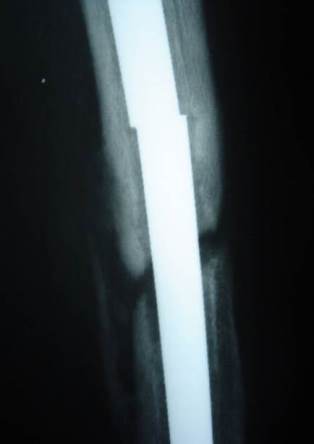

Nail parts after removal

• Middle part of the nail was removed by a small break in the lateral cortex.

• Distal part of the nail was removed by a hole distally in the lateral cortex then pushed by a drill pit and pulled through the medulla by an intestinal clamp.